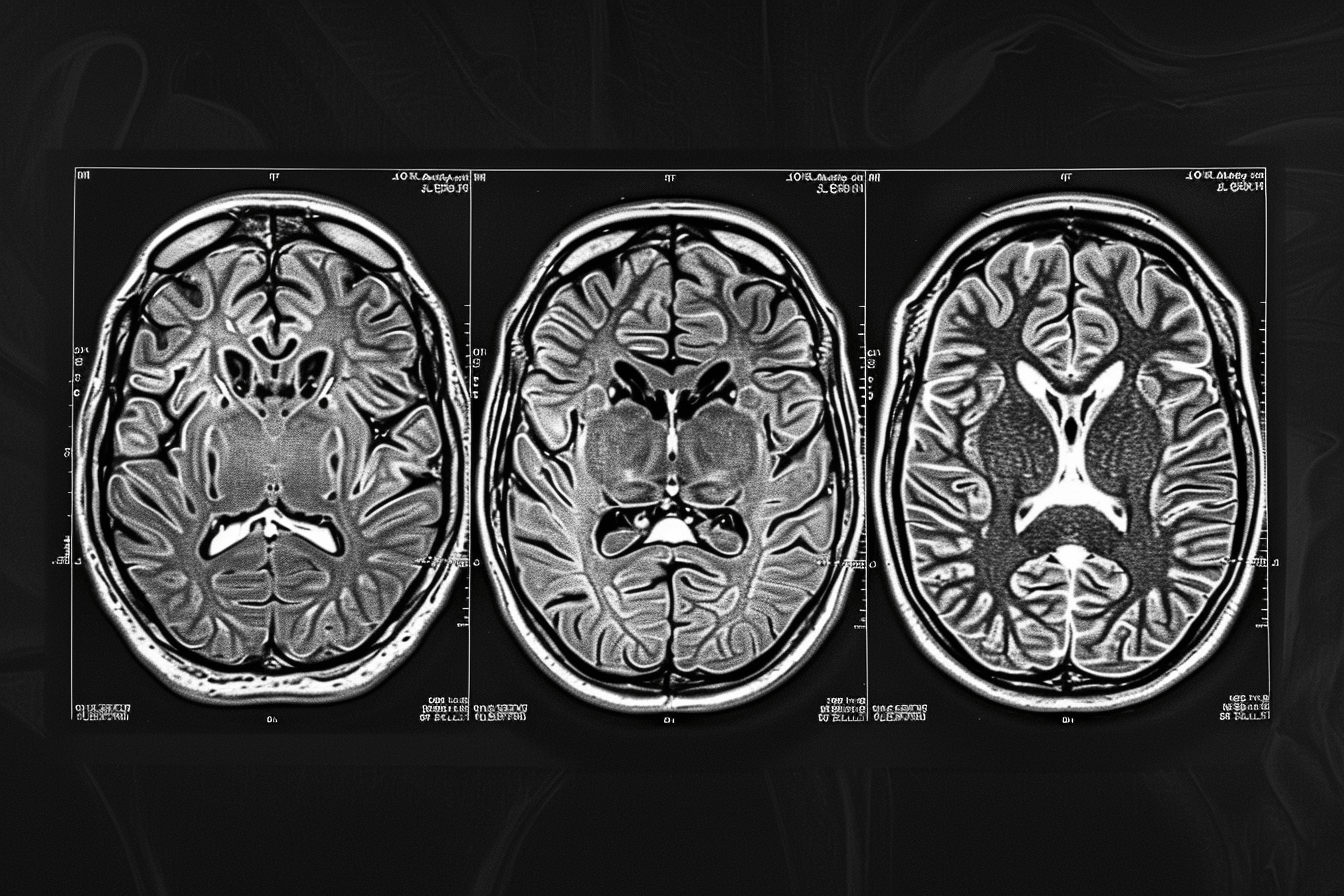

Silent Progression Phase (3 to 9 Months)

Between three to nine months after treatment, early biological regrowth may begin. Tumor cells start dividing, forming small clusters, and interacting with the surrounding brain environment.

During this phase, there are usually no clear symptoms, and MRI scans may still appear stable. This is the period where recurrence is developing but remains undetected. Clinical observations suggest that tumor activity can restart well before it becomes visible on imaging [9].

Early Detectable Recurrence (6 to 12 Months)

In many patients, recurrence becomes detectable within six to twelve months after initial treatment. At this stage, the tumor has grown enough to produce visible changes on MRI scans.

Symptoms may begin to reappear or gradually worsen. These can include headaches, cognitive decline, seizures, or neurological deficits depending on the tumor location. Studies show that a significant proportion of high-grade glioma patients experience recurrence within the first year [3].

Progressive Recurrence Phase (12 to 24 Months)

As time progresses, the tumor often becomes more aggressive. Between one to two years after treatment, recurrence is seen in the majority of high-grade glioma cases.

The regrown tumor may be more resistant to treatment due to prior exposure to radiation and chemotherapy. Clinical data indicates that most glioblastoma patients experience recurrence within this timeframe, and disease progression accelerates once it reappears [13].